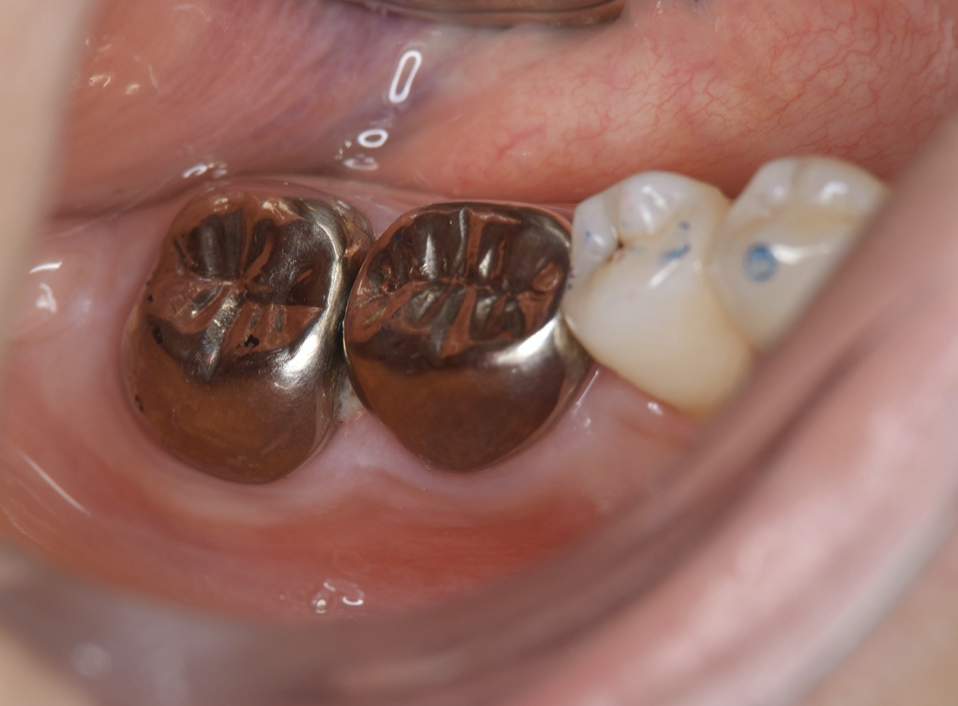

Full metal crowns were inserted for #46 and #47. Pathological mobility and bleeding on probing were not seen, and the transplanted tooth showed good function.

Figure 7.Inter-oral photo obtained after treatment. Full metal crowns were inserted for #46, #47. Pathological mobility and bleeding on probing were not seen, and the transplanted tooth showed good function.